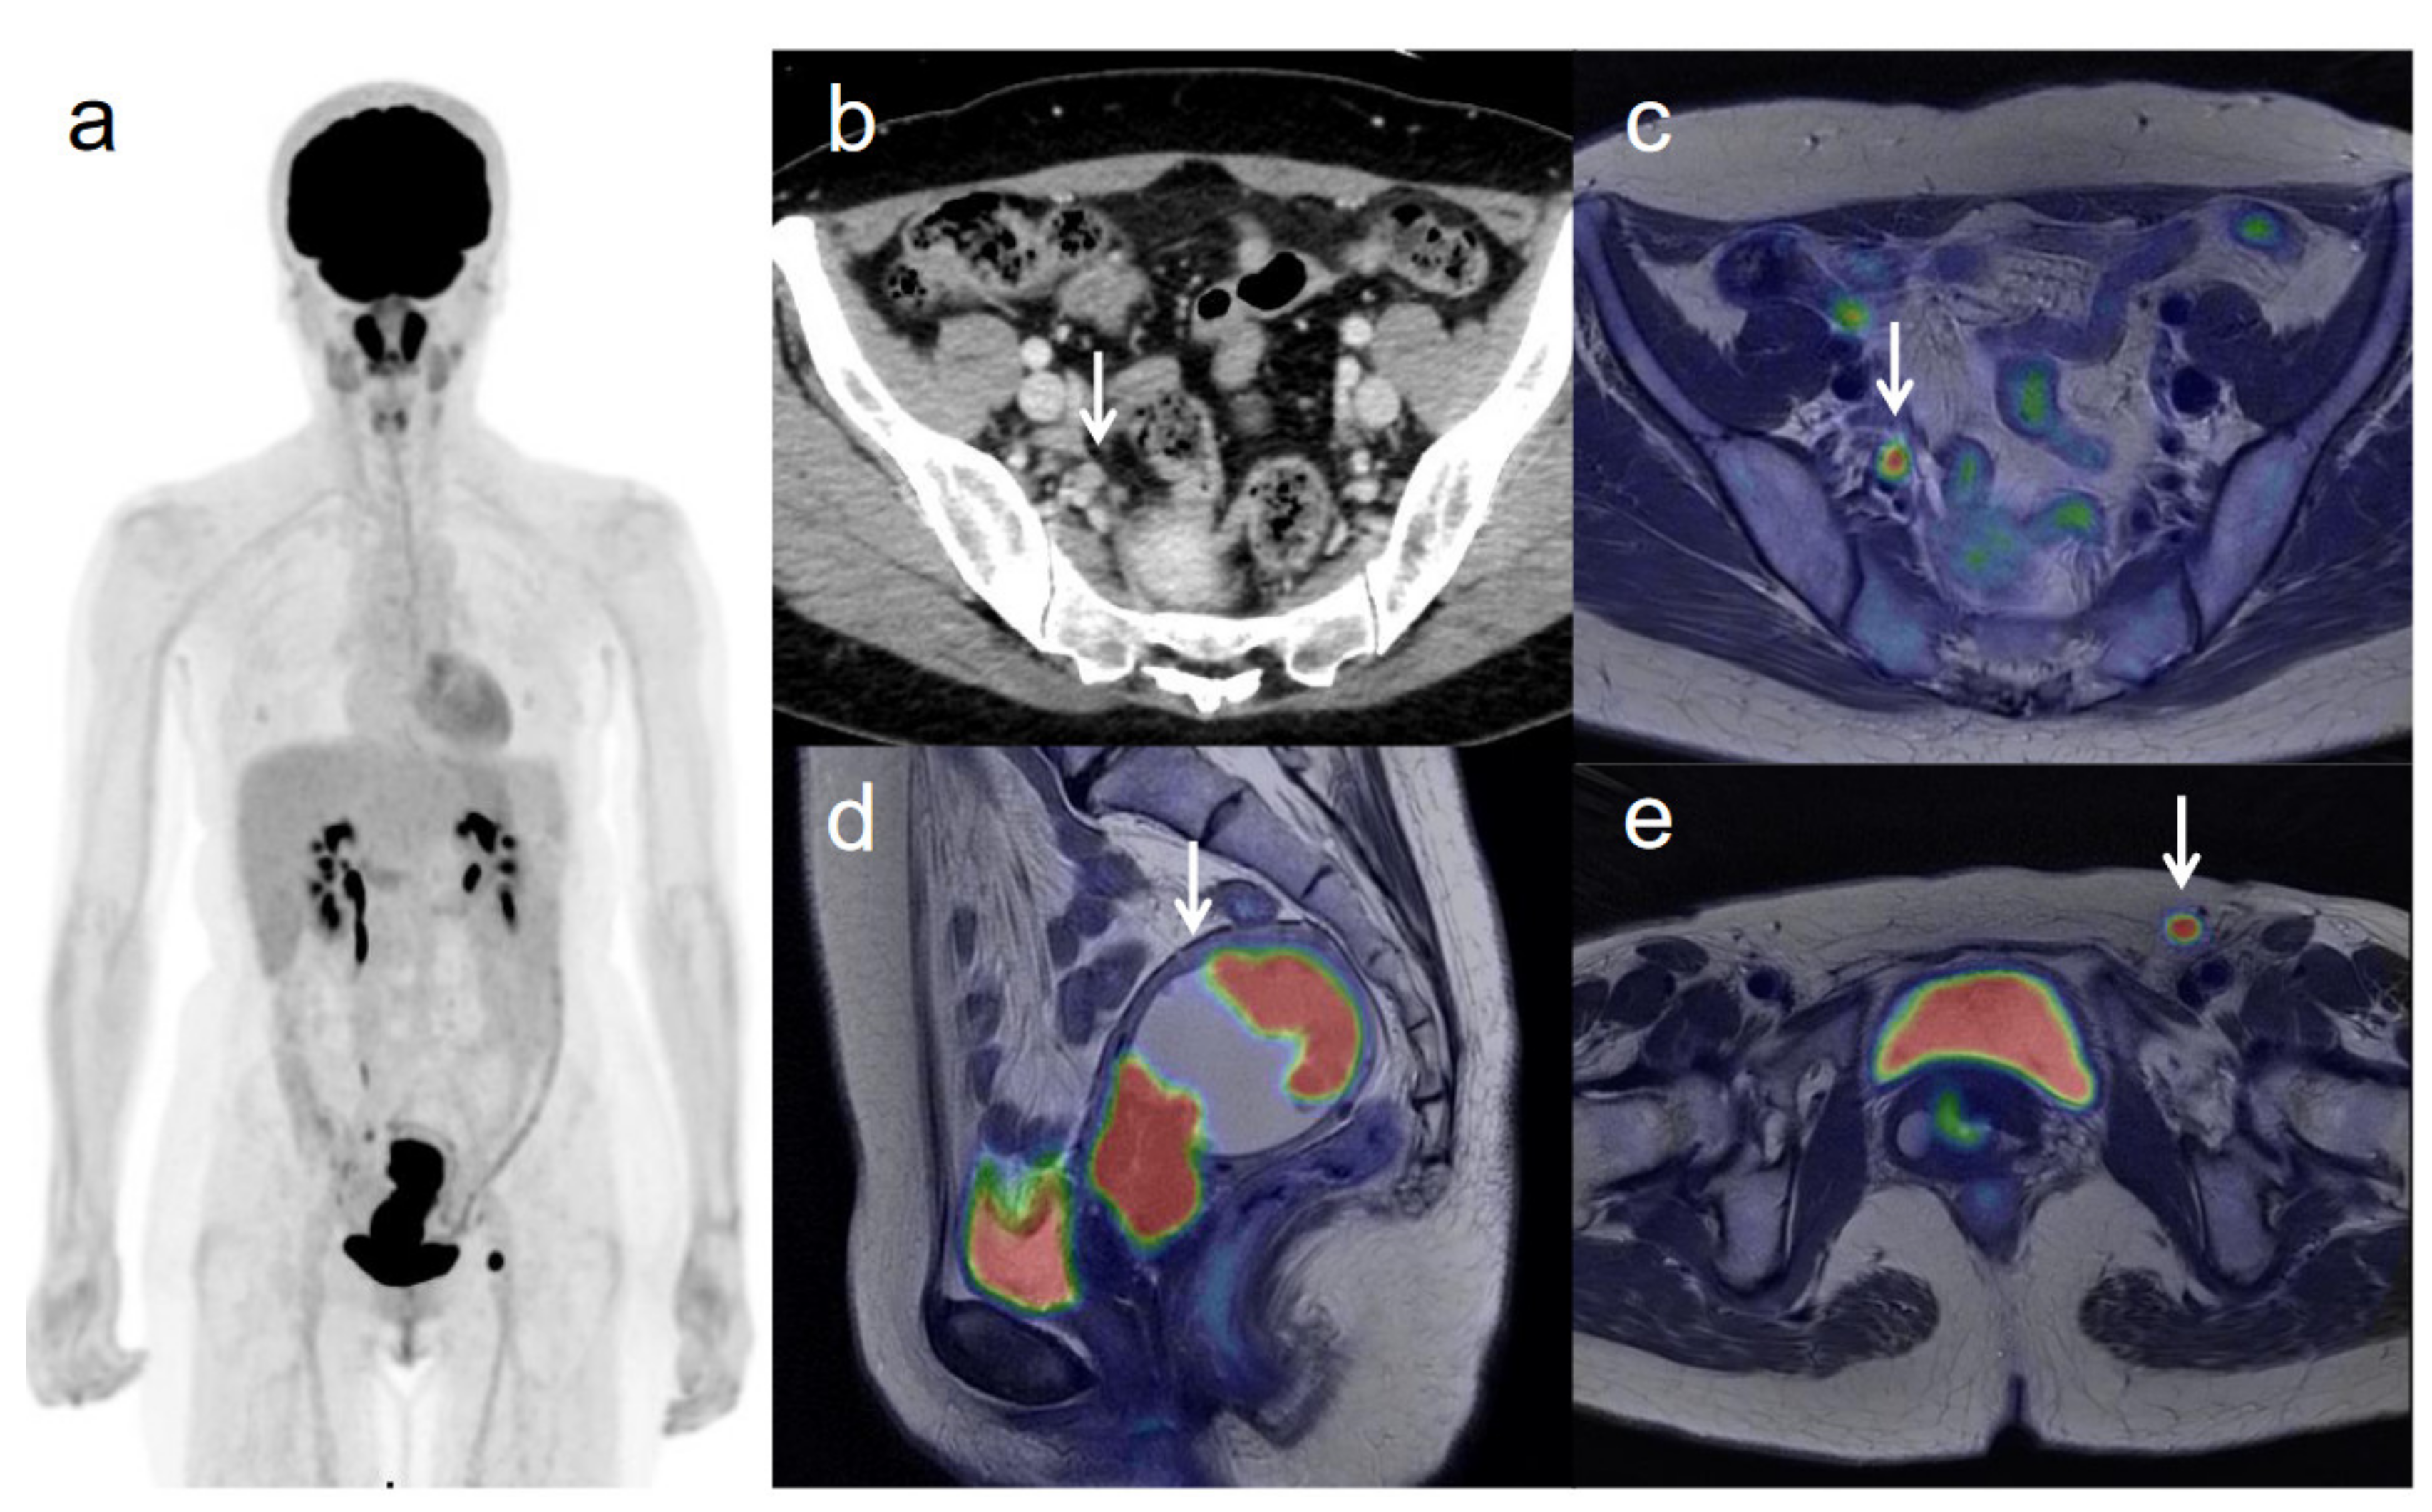

Figure 2. A 62-year-old woman with stage IVB cervical cancer with invasion into the pelvic side wall. (a) 18F-FDG PET image shows FDG uptake by tumor in the cervical cervix (arrow) and a right inguinal lymph node. (b) Axial T2-weighted pelvic MR image shows disruption of the right cervical stroma by the tumor and extension into the pelvic side wall (arrow). (c) Axial T2-weighted PET/MR image shows FDG uptake by the tumor, which invades the right cervical stroma and extends into the pelvic side wall (arrow). These appearances are consistent with the clinical findings. (d) Sagittal T2-weighted PET/MR image shows FDG uptake by the cervical tumor and invasion into the bladder (arrow). (e) Coronal T2-weighted PET/MR image shows invasion of the bladder by the cervical tumor and FDG uptake by a right inguinal lymph node (arrow).

3.3. Revised FIGO Staging